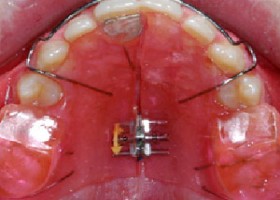

In conventional orthodontic treatment anchorage support usually taken from posterior teeth. In implant supported orthodontic treatment anchorage is taken from mini implants, which are inserted into the bone with minor surgical procedure. This technique can provide absolute anchorage, so that it can provide better aesthetic results.